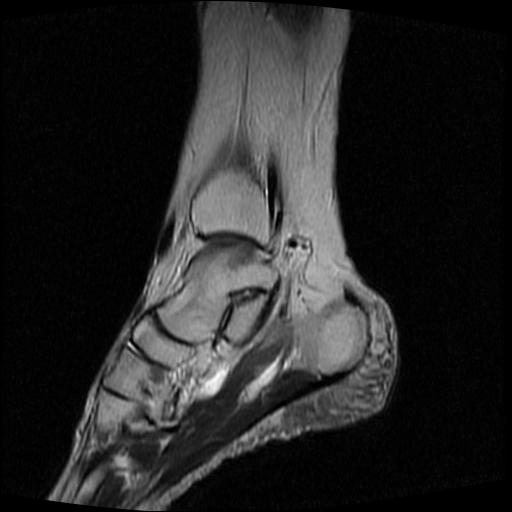

女性,70岁,右侧跟骨疼痛2个月,负重时加剧,不负重时不疼。

考虑: 跟骨骨髓炎.

跟骨cr片正常。

跟骨长t1长t2信号异常,边缘模糊(肿瘤一般边界清楚,故肿瘤不考虑),压脂像呈高信号--骨髓水肿(炎症?)。